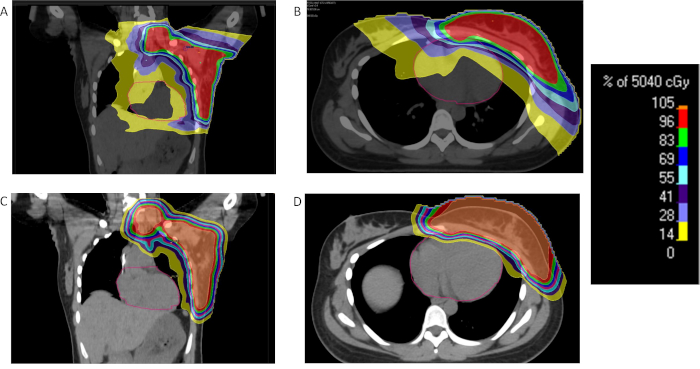

양성자 치료는 수소 원자의 핵인 양성자를 이용하여 특정 깊이에 도달했을 때 에너지를 집중적으로 방출하는 원리를 활용합니다. 이로 인해 암세포가 위치한 지점에만 강한 방사선 효과를 전달하고, 주변 건강한 조직에는 상대적으로 적은 영향을 주는 것이 특징입니다. 의료 전문가들은 특히 뇌종양, 소아암, 전립선암 등 정밀 치료가 필요한 분야에서 높은 효과가 기대된다고 설명하고 있습니다.